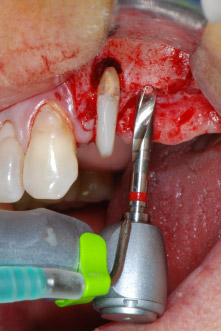

One month later, on the day of surgery, pain and inflammation at tooth 24 were minimal, but mobility of Miller class 2 was still present. After opening the flaps and cleaning the periapical and peri radicular infected tissue, the extent of the bone defect became obvious (Figs. 2 and 3).

At the buccal root, all vestibular and distal bone was missing. Attachment was essentially restricted to the palatal root, underlining the preliminary poor prognosis. Tooth 27 also showed a reduced horizontal attachment and a minimal apical rarefaction (cf. Fig. 1) without clinical symptoms.

Fig. 2 and 3: After raising flaps, one month after endodontic revision and initiation of full-mouth periodontal therapy, the buccal root of tooth 24 showed a total loss of bone and attachment.

However, we maintained our initial plan to retain both teeth as temporary bridge abutments during the six-months osseointegration period of the implants. At reentry, the situation would have to be reassessed. First, in an attempt to manage the endo-perio problem, the remaining root surface was carefully debrided with piezoelectric equipment (Piezomed, W&H, used with the spatula-shaped insert S1, originally designed for erosion of the lateral sinus wall) (Fig. 4).

Fig. 4: To preserve the tooth as a temporary abutment, the periodontium was debrided with piezoelectric equipment …

buccal apex of tooth 24

Fig 5: ... and the buccal apex of tooth 24 was abraded with the same instrument (apicoectomy).